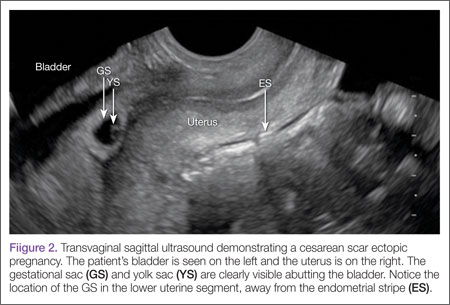

Regardless of one’s clinical suspicion, the diagnosis is made (or ruled out) through ultrasound. Uterine scar ectopic pregnancy is suspected when ballooning of the lower uterine segment is noted,1 when a trophoblast is seen at a presumed cesarean scar beneath the utero-vesicular fold, and when myometrium between the gestational sac and bladder wall is thin (<8 mm).2 As seen with this patient, the diagnosis is challenging as a uterine scar ectopic pregnancy can easily be mistaken for an intrauterine pregnancy. The clinician must make every effort to ensure that the pregnancy is surrounded by appropriate myometrium. It is much easier to diagnose an ectopic pregnancy far removed from the uterus, where the uterus and pregnancy are easily visualized and independent.